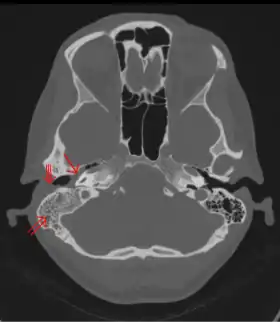

The diagnosis of mastoiditis is clinical—based on the medical history and physical examination. Imaging studies provide additional information; The standard method of diagnosis is via MRI scan although a CT scan is a common alternative as it gives a clearer and more useful image to see how close the damage may have gotten to the brain and facial nerves. Planar (2-D) X-rays are not as useful. If there is drainage, it is often sent for culture, although this will often be negative if the patient has begun taking antibiotics. Exploratory surgery is often used as a last resort method of diagnosis to see the mastoid and surrounding areas.[2][9]